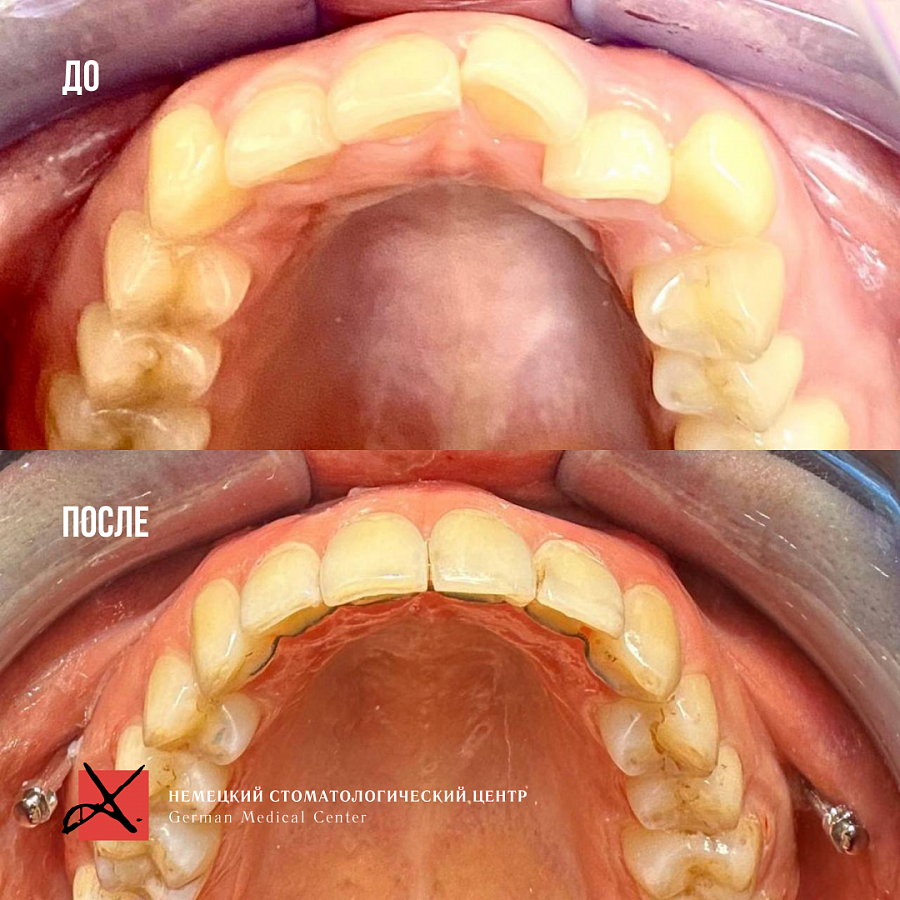

Комплексное гнатологическое и ортодонтическое лечение

Искривление зубных рядов, которое в свою очередь вызывало ряд гнатологических проблем: головная боль, боль в шейном отделе, боль ВНЧС, стираемость эмали и т.д.

Было проведено комплексное гнатологическое и ортодонтичечкое лечение. В результате пациент получил не только красивые ровные зубы, но и избавился от всех сопутствующих проблем.